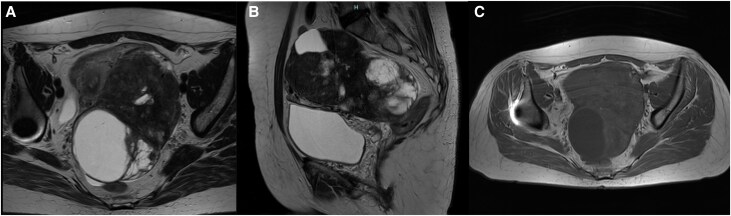

Ovarian carcinoid tumors (OCTs) are rare and may cause carcinoid syndrome (CS) even in the absence of liver metastases. Carcinoid heart disease (CHD), which develops in up to 50% of patients with CS, substantially affects morbidity and mortality. While prognosis is generally favorable, maintaining clinical suspicion and early diagnosis is crucial to prevent the development of advanced heart failure or metastases. We present a case of a woman exhibiting asthenia, diarrhea, and de novo severe hypertension. Echocardiography revealed typical features of CHD. Elevated urinary levels of 5-hydroxyindoleacetic acid (5-HIAA) corroborated the diagnosis of CS. 68Ga-DOTANOC positron emission tomography computed tomography identified a suspicious left pelvic mass, which was subsequently confirmed by magnetic resonance imaging. Surgical resection of the tumor was performed, followed by tricuspid valve replacement surgery, confirming the diagnosis of OCT associated with CS and CHD. Postoperative follow-up revealed considerable clinical improvement, and the patient has remained free of recurrence. This case underscores the complex cardiovascular involvement in CS, with secondary hypertension as the initial symptomatic manifestation, which improved following resection of OCT. Additionally, it highlights the role of CS in the pathogenesis of severe tricuspid valve dysfunction, which ultimately required cardiac surgery.